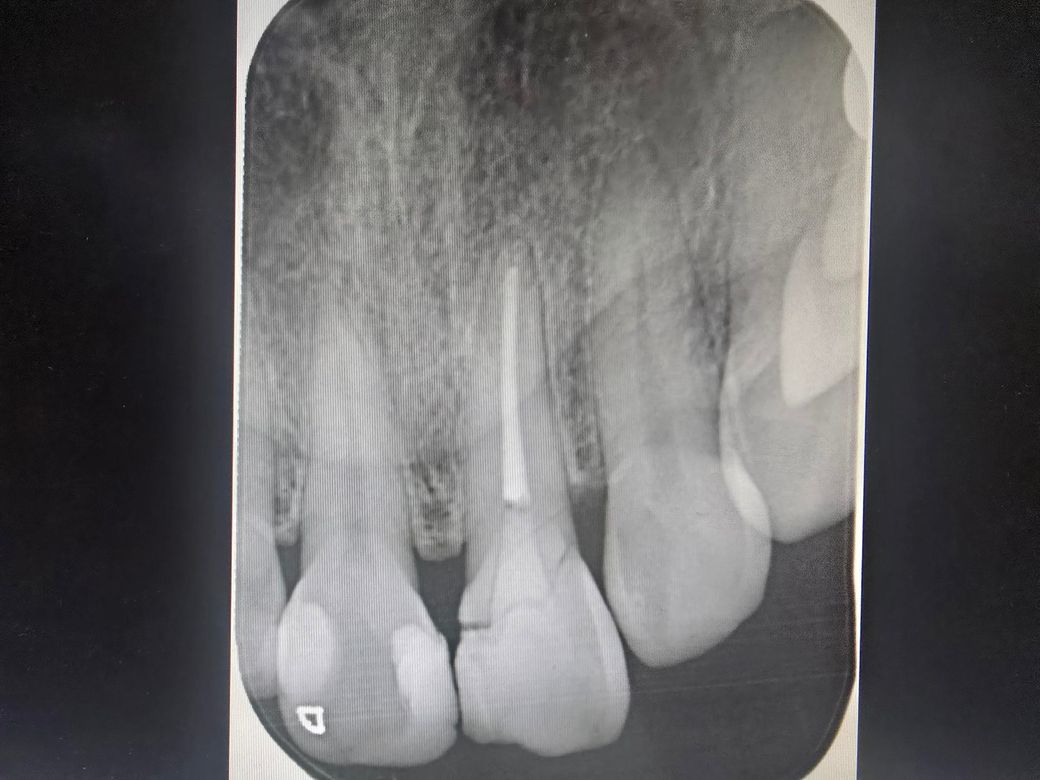

파절 치근단염증? 이럴경우 살릴수있나요? 넘 아파요

옆에있는 이빨도 끝쪽 금간거같은데 맞나요?

찾아보니 치근단염증 증상입니다.

첨부해주신 사진을 보니 파절선이 굉장히 크고 명확합니다.

치아 머리 부위는 파절편 살릴 순 없을 것 같고요 위에는 분리해서 빼고 아래 남은 쪽에 기둥박고 레진코어쌓고 크라운 씌우는 치료를 해볼 순 있으나 예후는 좋지 않습니다 즉 오래쓰지 못할 가능성이 높고 그럴거면 임플란트 하는게 나을 수도 있습니다

앞니 옆 치아는 엑스레이상으론 파절양상은 없습니다